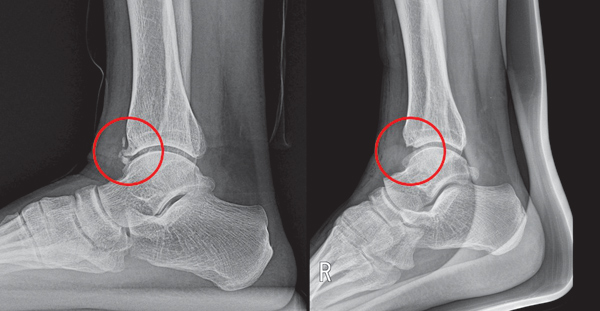

14. 발목 인대 손상 후유증

- 원인: 발목 염좌 이후 발바닥까지 통증이 퍼짐.

- 특징: 발목 불안정, 발바닥 하중 불균형.

- 위험 요인: 이전 발목 부상 이력.

- 대처법: 재활운동, 발목 보호대 착용.